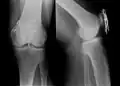

Eine Bimalleolarfraktur im seitlichen Röntgenbild … -

… und von vorne … -

… mit Zuggurtung am Innenknöchel und Platte am Außenknöchel versorgt